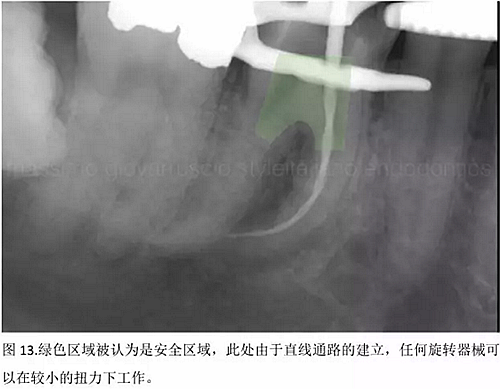

結(jié)論:本文的目的是描述一種旨在優(yōu)化根管根尖部分預(yù)備的預(yù)敞技術(shù)。根管頸部或冠方的早期預(yù)敞對(duì)于減少初尖銼直徑和根尖部根管直徑之間的差異至關(guān)重要。大量研究表明,手用或機(jī)用器械預(yù)敞根管能顯著減少器械折斷的發(fā)生率。下一篇文章將描述如何建立可重復(fù)的引導(dǎo)路徑。而引導(dǎo)路徑是指鎳鈦器械可沿著光滑根管壁輕易地滑行至工作長(zhǎng)度的通路。